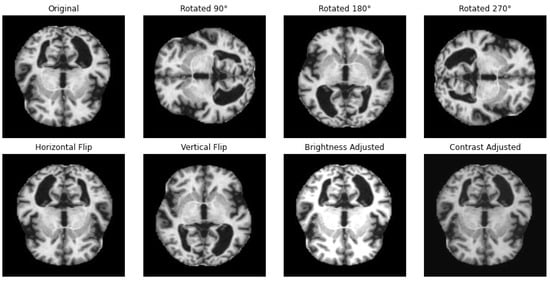

A Hybrid Convolutional Neural Network–Long Short-Term Memory (CNN–LSTM)–Attention Model Architecture for Precise Medical Image Analysis and Disease Diagnosis

Background: Deep learning (DL)-based medical image classification is becoming increasingly reliable, enabling physicians to make faster and more accurate decisions in diagnosis and treatment. A plethora of algorithms have been developed to classify and analyze various types of medical images. Among them, Convolutional Neural Networks (CNNs) have proven highly effective, particularly in medical image analysis and disease detection. Methods: To further enhance these capabilities, this research introduces MediVision, a hybrid DL-based model that integrates a vision backbone based on CNNs for feature extraction, capturing detailed patterns and structures essential for precise classification. These features are then processed through Long Short-Term Memory (LSTM), which identifies sequential dependencies to better recognize disease progression. An attention mechanism is then incorporated that selectively focuses on salient features detected by the LSTM, improving the model’s ability to highlight critical abnormalities. Additionally, MediVision utilizes a skip connection, merging attention outputs with LSTM outputs along with Grad-CAM heatmap to visualize the most important regions of the analyzed medical image and further enhance feature representation and classification accuracy. Results: Tested on ten diverse medical image datasets (including, Alzheimer’s disease, breast ultrasound, blood cell, chest X-ray, chest CT scans, diabetic retinopathy, kidney diseases, bone fracture multi-region, retinal OCT, and brain tumor), MediVision consistently achieved classification accuracies above 95%, with a peak of 98%. Conclusions: The proposed MediVision model offers a robust and effective framework for medical image classification, improving interpretability, reliability, and automated disease diagnosis. To support research reproducibility, the codes and datasets used in this study have been publicly made available through an open-access repository. Full article

Show Figures

Figure 1